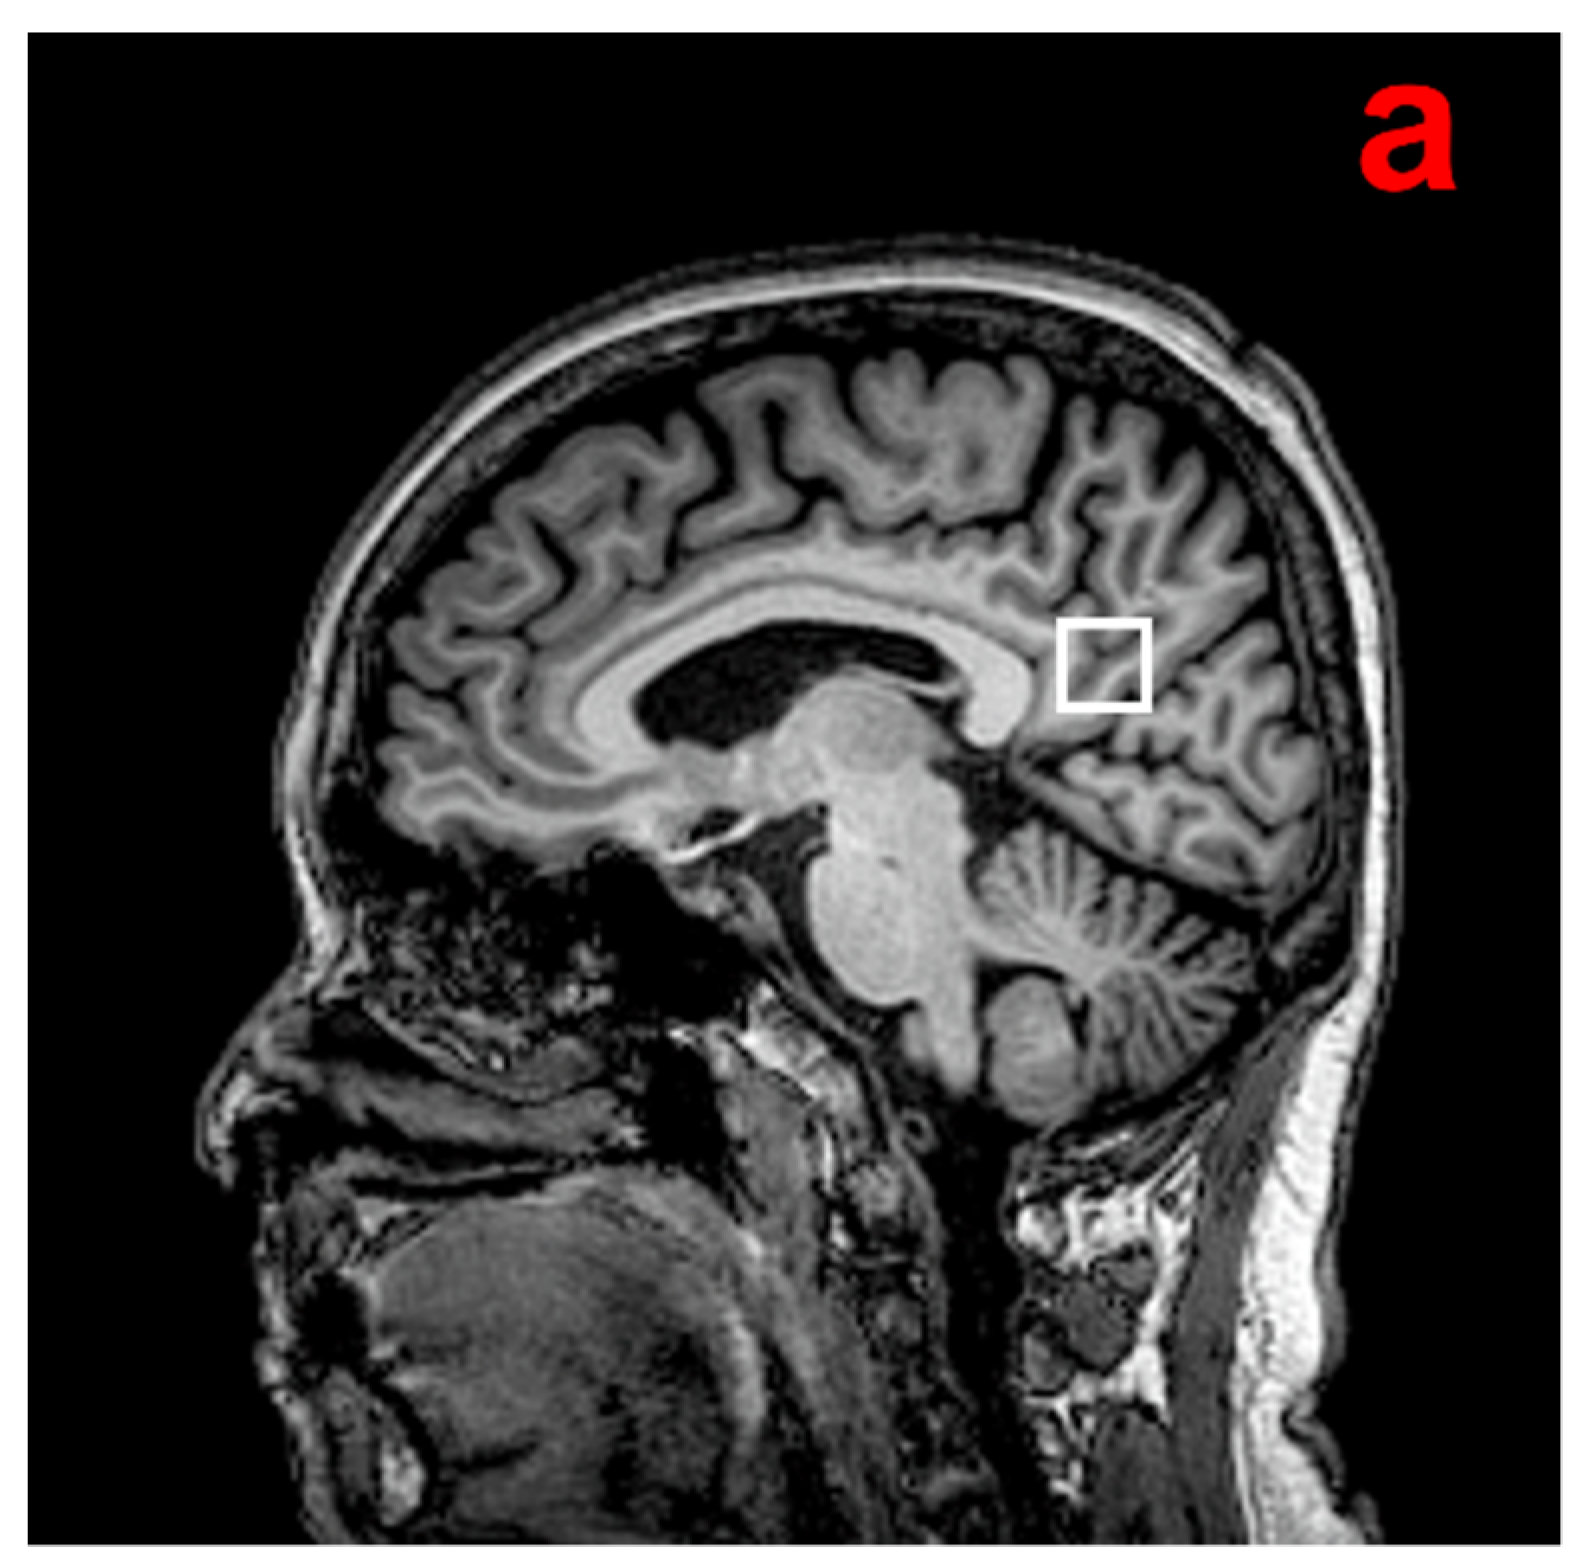

2.5. 1H-MRS Acquisition and Analysis